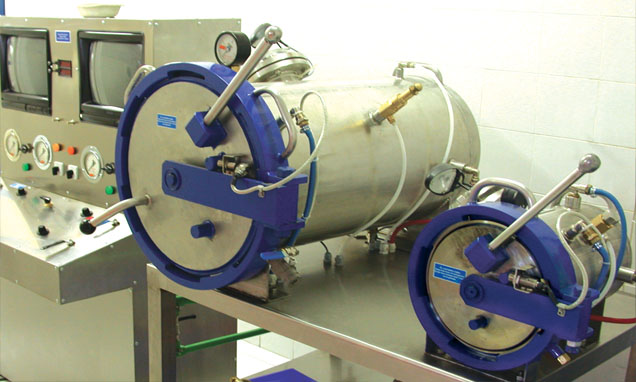

Lječenje dekompresijske bolesti

Terapija

kisikom